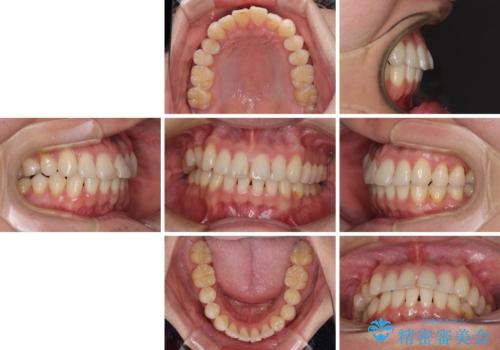

- 以前矯正治療を行ったものの、思い通りの仕上がりではなく、更には後戻りが気になってきたとのことで来院された患者様です。

上顎右側の第一小臼歯が動きにくい歯であり、以前矯正治療を行った際に傾斜した位置のまま終了したことと、それに伴い後戻りで歯列が波打っているようになっていることを大変気にしていらっしゃいました。

咬合平面改善のため、アンカースクリューを多用し、ワイヤー装置にて矯正治療を行うこととしました。

動きにくい歯はやはり動きにくく、咬み合わせ改善に時間を要しましたが、患者様には大変満足していただけました。